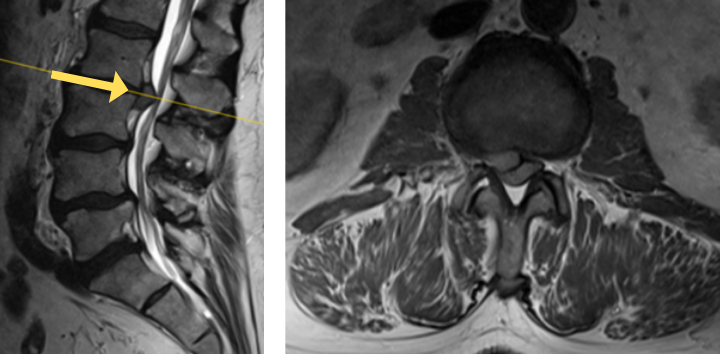

The grade 1 spondylolisthesis at L4/L5 requires both decompression at the L4/L5 level but also fusion because of the instability with motions. Here are three standing x-rays: one in the neutral position, one in flexion, and one in extensions. Notice the movement in the vertebral bodies at L4 and L5. This is abnormal motion and it can contribute to back pain and increase stenosis in certain positions. Thus, it requires decompression and stabilization with fusions.

Image 2. This shows the lumbar spine in motion. Notice the L4 and L5 level changes with flexion and extension. Notice the L2 and L3 levels do not have that type of motion. This is instability.

The herniated disc only requires decompression and removal of the herniated disc. Notice in the same flexion extension dynamic x-rays. There’s no abnormal motion at the L2/L3 level.